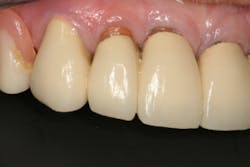

Dentition: Upper anterior splinted crowns had open margins and caries. Radiographs confirm decay, along with open margins (figures 6–11). Lower incisal anterior wear noted (figure 2).

Periodontium: Probing depths normal on all teeth, with some bleeding noted around the margins of the upper splinted crowns. Slight to moderate bone loss on lower anterior teeth.

This clinical case began with a frustrated 75-year-old patient, who, after many years of failed attempts to repair the functional problem, came to the realization that a different solution was in order. The existing problem of an upper removable precision attachment partial denture was addressed first. The issue at hand was that the partial denture was perforated at the precision attachments, with the upper left side being more significant compared to the right side (figures 1–5). As a result, retention was adequate on the right side, but limited on the left. The patient was also concerned about esthetics, but needed a solution that kept a restricted budget in mind.